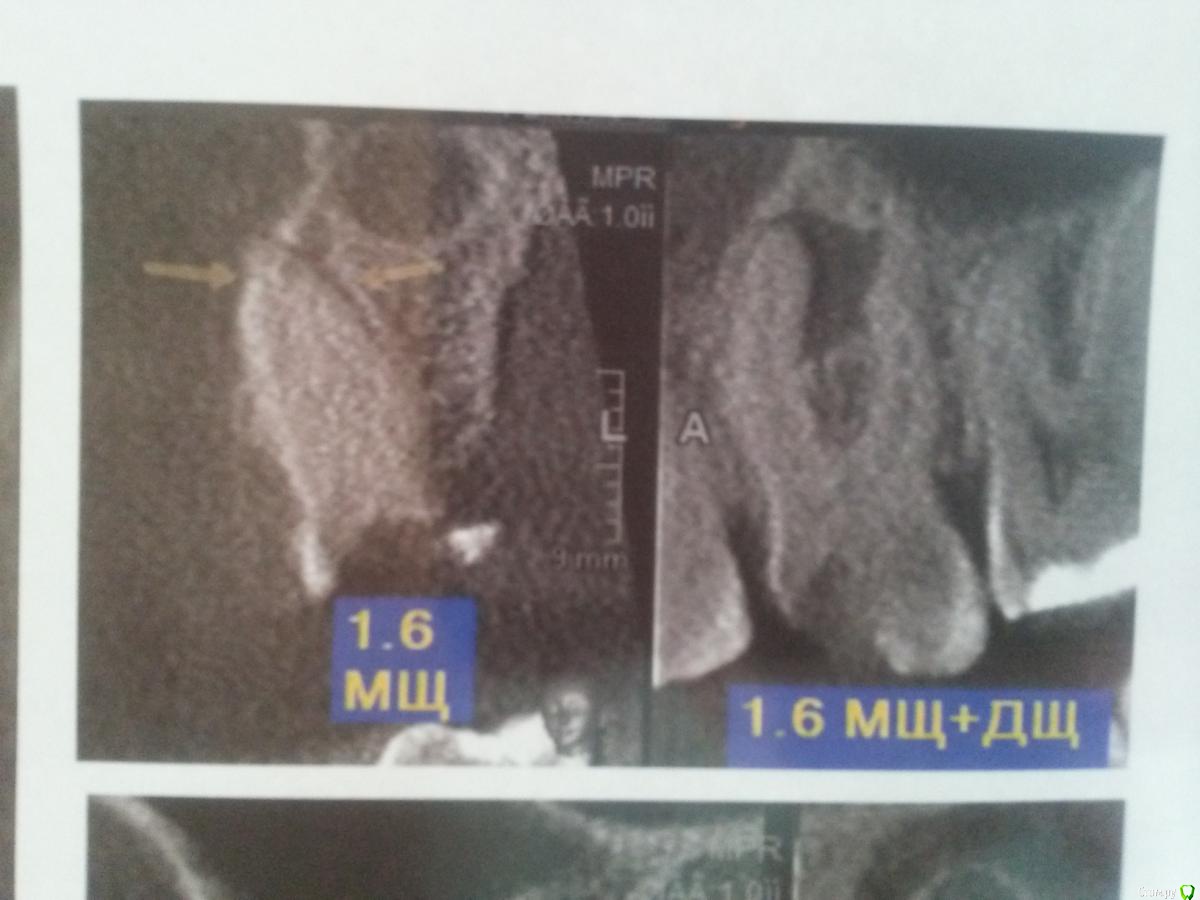

strator Опубликовано 4 мая, 2015 Автор Поделиться Опубликовано 4 мая, 2015 Это было в Москве или в другом городе? Сколько лет назад?дело было в Липецке лет 20 назад... Выкладываю описание и снимки проблемного зуба Ссылка на комментарий

strator Опубликовано 4 мая, 2015 Автор Поделиться Опубликовано 4 мая, 2015 продолжение снимков проблемного зуба Ссылка на комментарий

strator Опубликовано 13 мая, 2015 Автор Поделиться Опубликовано 13 мая, 2015 посмотрела описание своего КТ. указано, что у меня 4 канала, а судя по оплаченному мною счету лечили мне только 3 канала.подскажите, пожалуйста, сейчас хожу с лекарством получается в 3 каналах и временной пломбой. надо ли бежать к врачу и говорить еще об одном канале, либо до следующего посещения врача о забытом канале пока не думать? бывает ли такое, что врач не находит каналы? если все же у меня их 4, как в описании КТ, то по правильному врач заново должен все обработать и опять ходить с лекарством, либо он может уже начать полностью пломбировать все постоянно? спасибо. Ссылка на комментарий